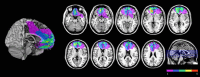

Figure 1.

Location and overlap of brain lesions of the nine subjects with VMF damage, projected on axial slices of the MNI brain. Different colors indicate the number of subjects who had damage involving a particular area in common, as indicated in the color key.